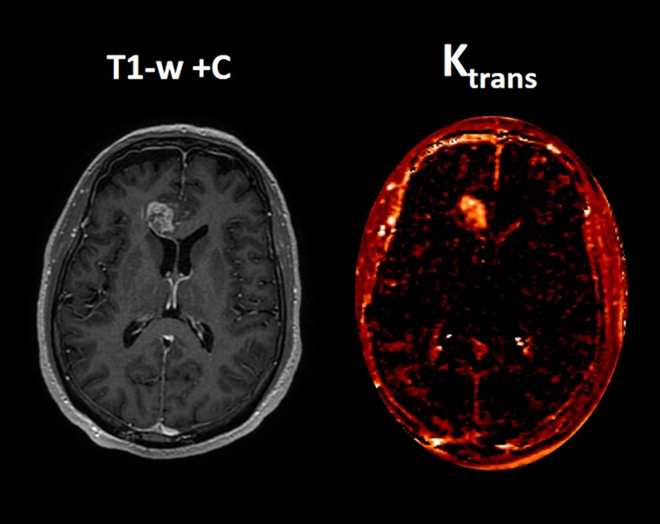

Perfusion MRI quantifies hemodynamic properties of brain tissue. Perfusion maps represent physiological measurements rather than simple color patterns. Parameters such as relative cerebral blood volume (rCBV) or permeability metrics (e.g., Ktrans) provide insight into vascular activity within lesions (Figure 5).

In tumor follow-up, these values can help distinguish tumor recurrence from radiation necrosis. Regions with high rCBV and permeability typically indicate active tumor tissue, while lower values may suggest treatment-related changes. Such quantitative measurements support more confident clinical decision-making.

Figure 3. Quantitative dynamic contrast-enhanced (DCE) perfusion MRI in a representative high-grade glioma. (A) Axial post-contrast T1-weighted image (T1-w +C) showing a heterogeneously enhancing intra-axial mass lesion. (B) Corresponding Ktrans map. Quantitative T1 DCE analysis converts signal changes and contrast concentration into specific numerical biomarkers. The solid enhancing component demonstrates markedly elevated Ktrans of 0.13 min⁻¹ (red-yellow areas), reflecting increased vascular permeability and blood–brain barrier disruption. This finding is highly suggestive of an active high-grade neoplastic process (e.g., glioblastoma or metastasis) rather than a low-grade glioma or non-neoplastic inflammatory lesion. Courtesy of Christos Tsiotsios (Author).